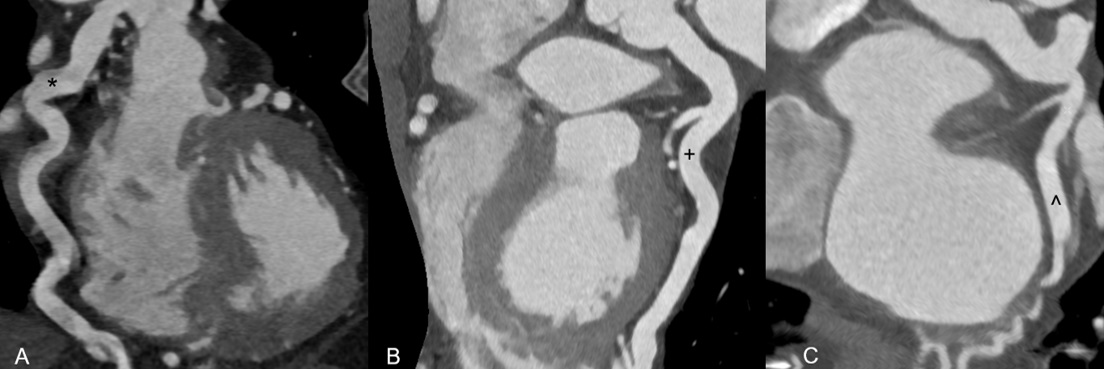

Selective left coronary angiography showed an ectatic left main artery and tortuous collaterals from the proximal left anterior descending (LAD) artery to a severely ectatic right RCA. The LAD was also severely ectatic and filled late. Retrograde filling of the pulmonary artery from the RCA was visualized (Figure 1, Video 1). We were unable to engage the RCA selectively with multiple diagnostic catheters. Ascending aortography confirmed absence of RCA ostium from the aorta and suggested the diagnosis of anomalous right coronary artery from pulmonary artery (ARCAPA) (Figure 2, Video 2). CT angiography confirmed ARCAPA with large left-to-right collaterals from LAD to RCA (Figures 3-5). There were no other congenital heart anomalies. Echocardiography showed normal biventricular function and normal chamber sizes. A myocardial perfusion Single Photon Emission Computed Tomography (SPECT) study showed a moderate intensity, medium-sized, partially reversible defect in the RCA distribution. The patient was referred to cardiothoracic surgery for consideration of reimplantation of the RCA to the aorta. However, due to her asymptomatic status at baseline, the decision was made to pursue initial conservative management.